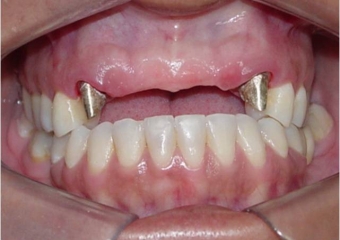

Imagem inicial